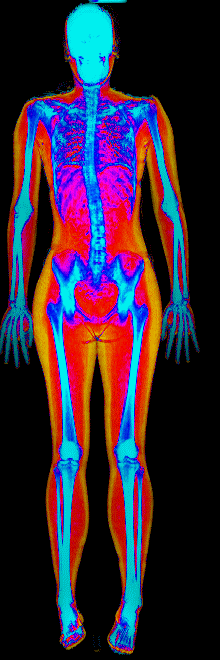

What Fat Loss Looks Like on a DEXA Scan

Lost 30.2 lb of fat, gained 3.9 lb lean · 240 → 214 lb · Age 43

Lost 27.9 lb of fat · 225 → 191 lb · Age 40

Lost 23.7 lb of fat · 186 → 155 lb · Age 34